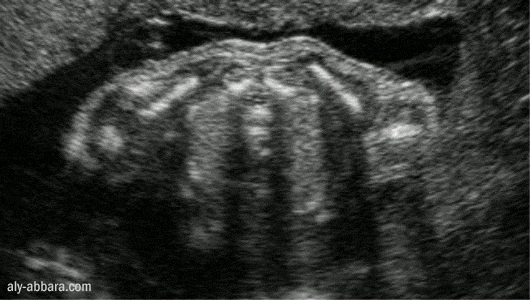

Les deux omoplates fœtales

Coupe transversale

Il s'agit d'une grossesse à 26 semaines d'aménorrhée